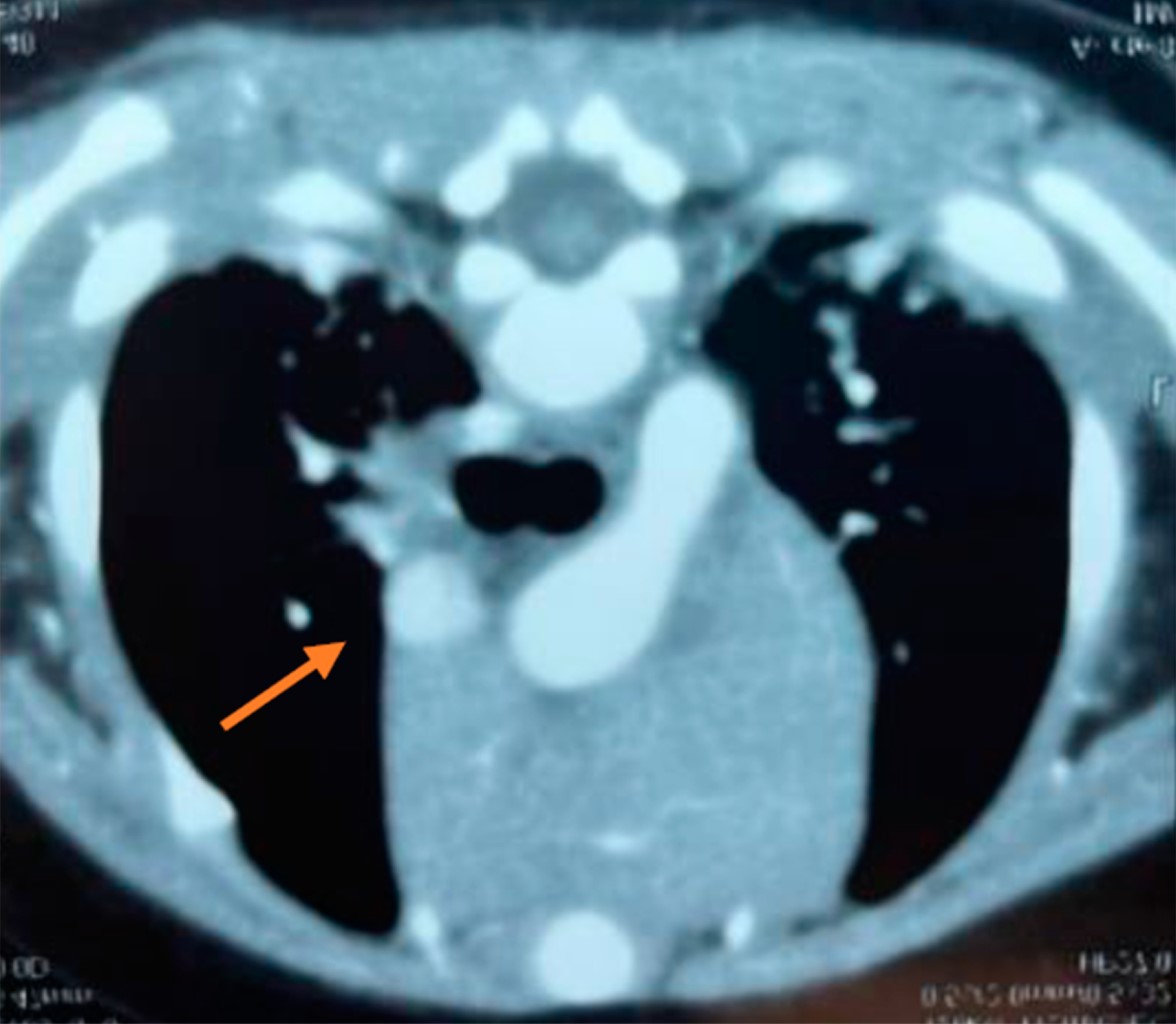

Intracardiac hemangioma in an infant

Introduction: intracardiac tumors in children are rare, but most are benign. In general, these tumors do not cause symptoms, but as they increase in size, they can lead to heart failure. Case presentation: three-month-old male patient who had an intrauterine diagnosis of mediastinal mass. At birth he was asymptomatic. Resection of right atrial tumor was performed. The pathology report indicated that it was an intracardiac hemangioma. The patient has had a favorable evolution. Conclusions: intracardiac tumors are a rare entity in pediatrics, which are generally detected accidentally.

Figure 3